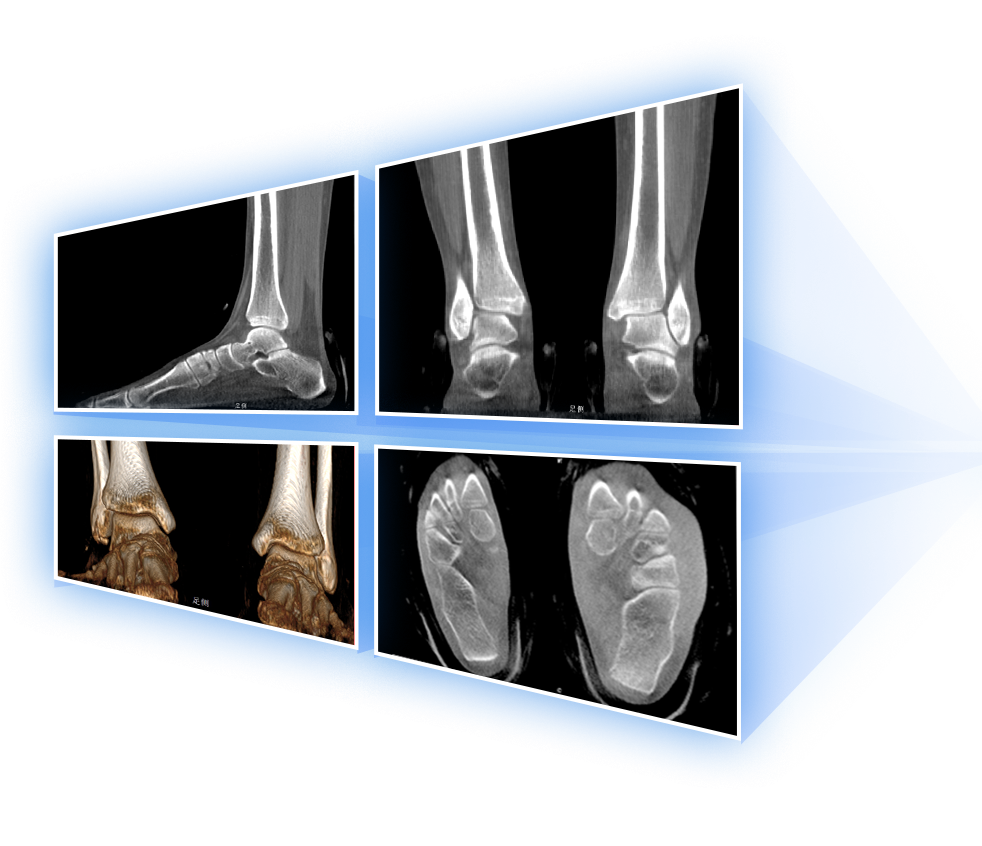

· 補位CT,提供負重位三維影像

獨特的負重位三維影像

填補常規CT/MR空白

助力術前規劃和術后評估

• 足踝

2D+3D一站式快速檢查

支持雙腿或雙側髖關節掃描 | 方便對比,降低漏診誤診